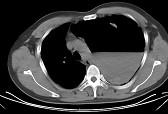

女,6岁,胸闷,咳嗽,胸部CT如图,最可能的诊断为 ( )A.畸胎瘤B.右侧液气胸C.右肺肺大疱D.右侧脓胸E.支气管囊肿并感染